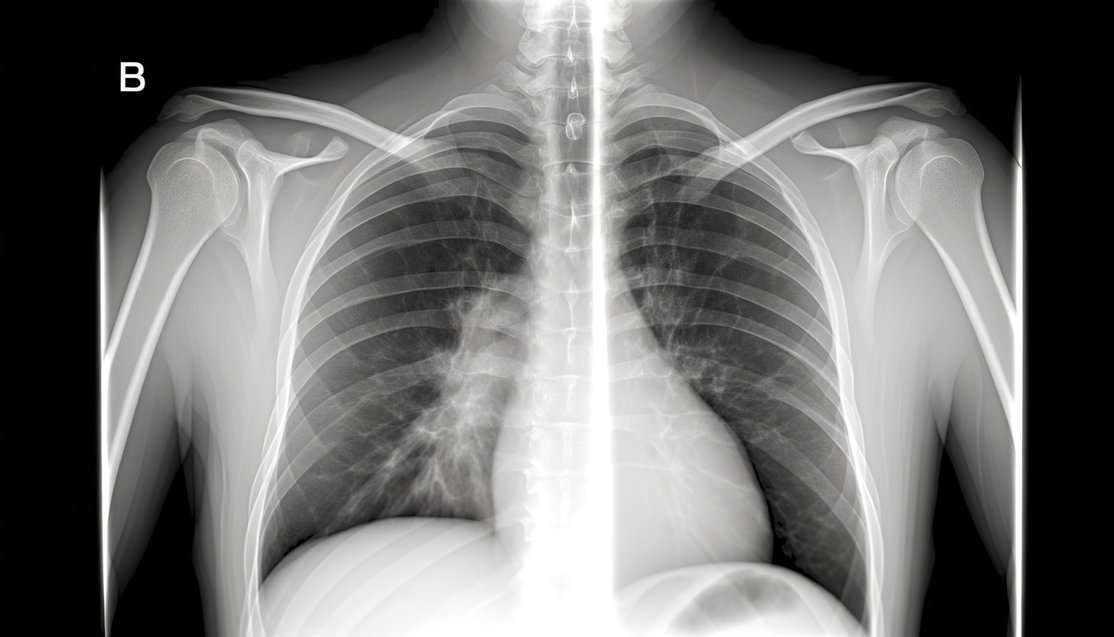

На первом осмотре имеет место изучение истории, анализ жалоб, визуальный осмотр. Далее специалист назначает лабораторную диагностику – это анализ крови, мочи, анализ таких показателей, как мочевина, уровень С-белка, ЛДГ, ферменты печени (АЛТ, АСТ). При необходимости выполняется коагулограмма. По назначению врача пациент проходит инструментальное обследование – рентген скелета (в двух проекциях), КТ, МРТ, ПЭТ с использованием радиоактивного препарата, цитогенетический анализ. Чтобы определить уровень распространенности рака, специалист выполняет пункцию и биопсию – анализ образца костной ткани под микроскопом (клетки опухоли имеют синюшный оттенок).